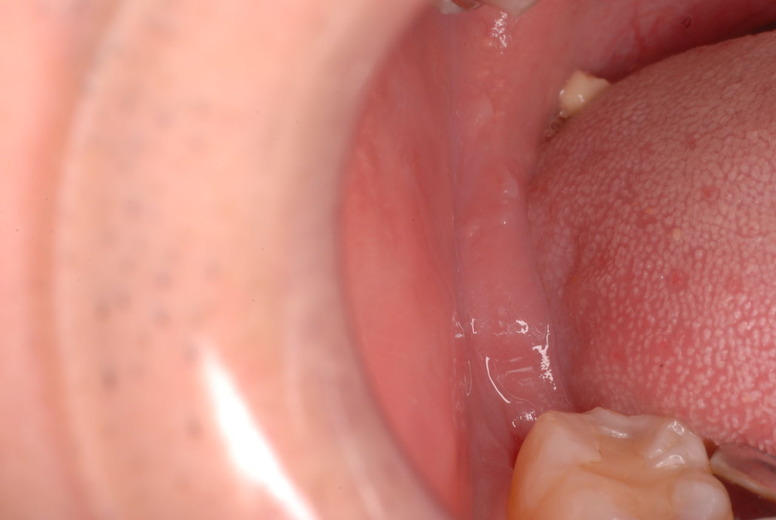

写真左下の親知らずが痛くなり抜歯しました。その後歯茎を除去して虫歯を露出させる処置を二回ほどしています。

レントゲンでは小さいですが、こう言う虫歯が一番怖いのです。

治療の成功率は極めて悪くすぐ再発しやすいのです。